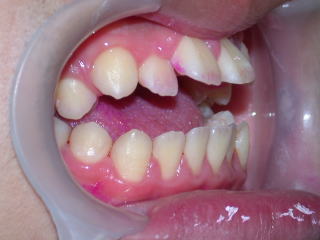

平成23年9月17日(第一小臼歯4本抜歯症例です)